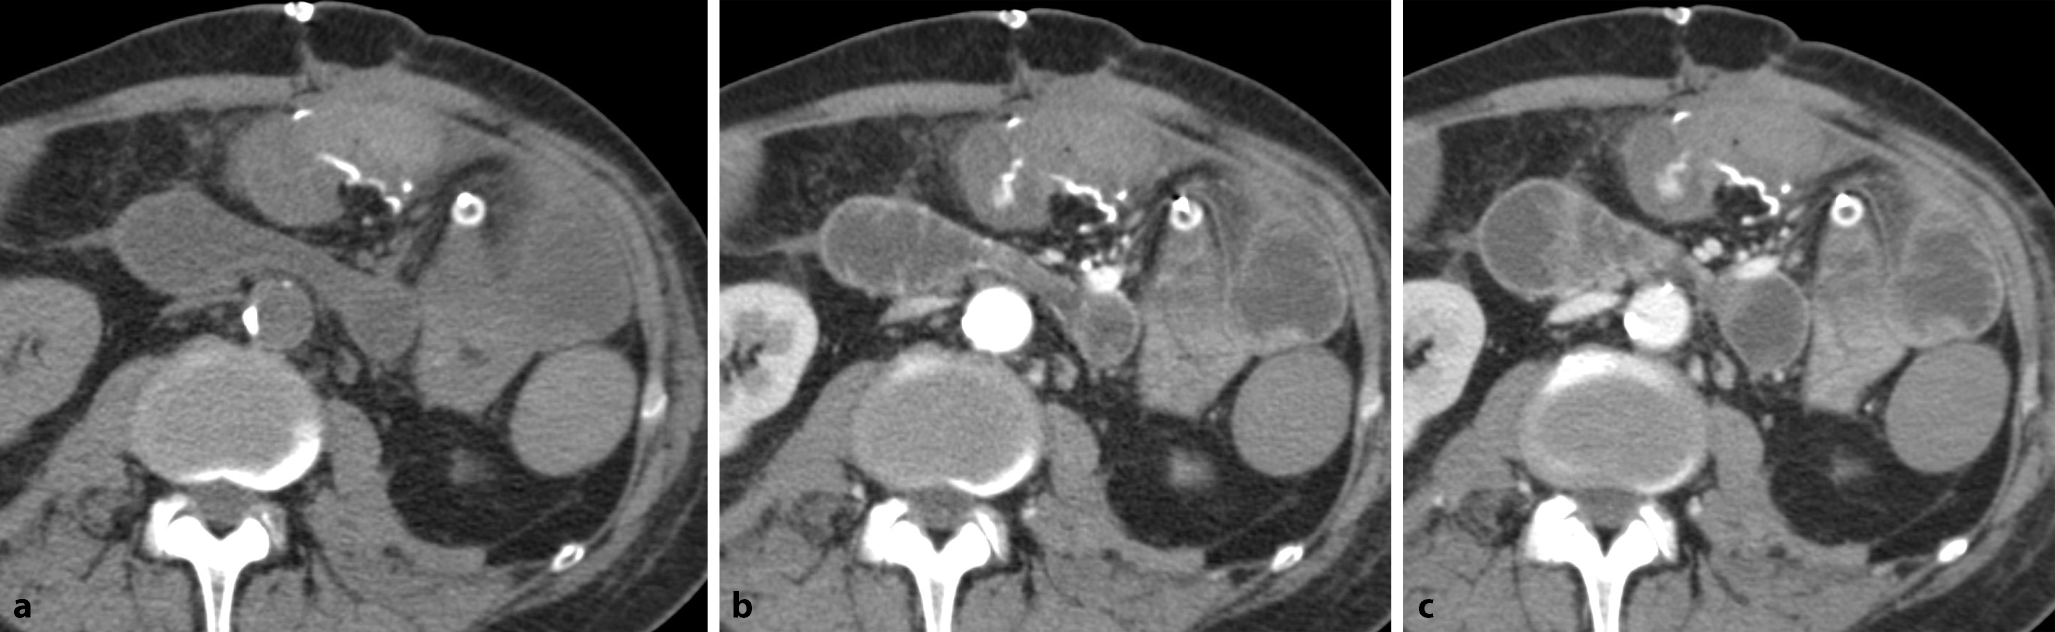

Im Anschluss erfolgt eine Computertomographie (CT) des Abdomens mit intravenösem Kontrastmittel (Abb. 1).

Abb. 1

Die Sonographie des rechten Oberbauchs (a) mit einem hoch auflösenden Linearschallkopf zeigt das blinde Ende der Seit-zu-Seit-Enterokolostomie. b,c Venöse Computertomographie des Abdomens mit Nahtmaterial im Bereich der Anastomosenregion, b Verlauf des neoterminalen Ileums (Pfeile)

Auflösung Kasuistik

Die hoch auflösende Darmsonographie des Abdomens zeigte eine lineare echoreiche Struktur, die sich über das blinde Ende der enterokolischen Anastomosenregion erstreckte. Das umgebende Fettgewebe zeigte echoreiche ödematöse Veränderungen. In der weiterführenden CT des Abdomens wurde eine von der Anastomose ausgehende Fistelformation bestätigt. Die Patientin musste erneut operiert werden (erweiterte Ileoaszendostomie). Nach 5 Monaten präsentiert sie sich mit normalisiertem Calprotectin und einem endoskopischen Ansprechen (Rutgeerts-Score i2a; Abb. 8). Mit der leicht verfügbaren Ultraschalluntersuchung konnte der Verdacht einer Fistulierung gestellt werden, mit einer CT-Akutuntersuchung ließ sich dieser Verdacht bestätigen und eine zeitnahe weiterführende chirurgische Sanierung ermöglichen.